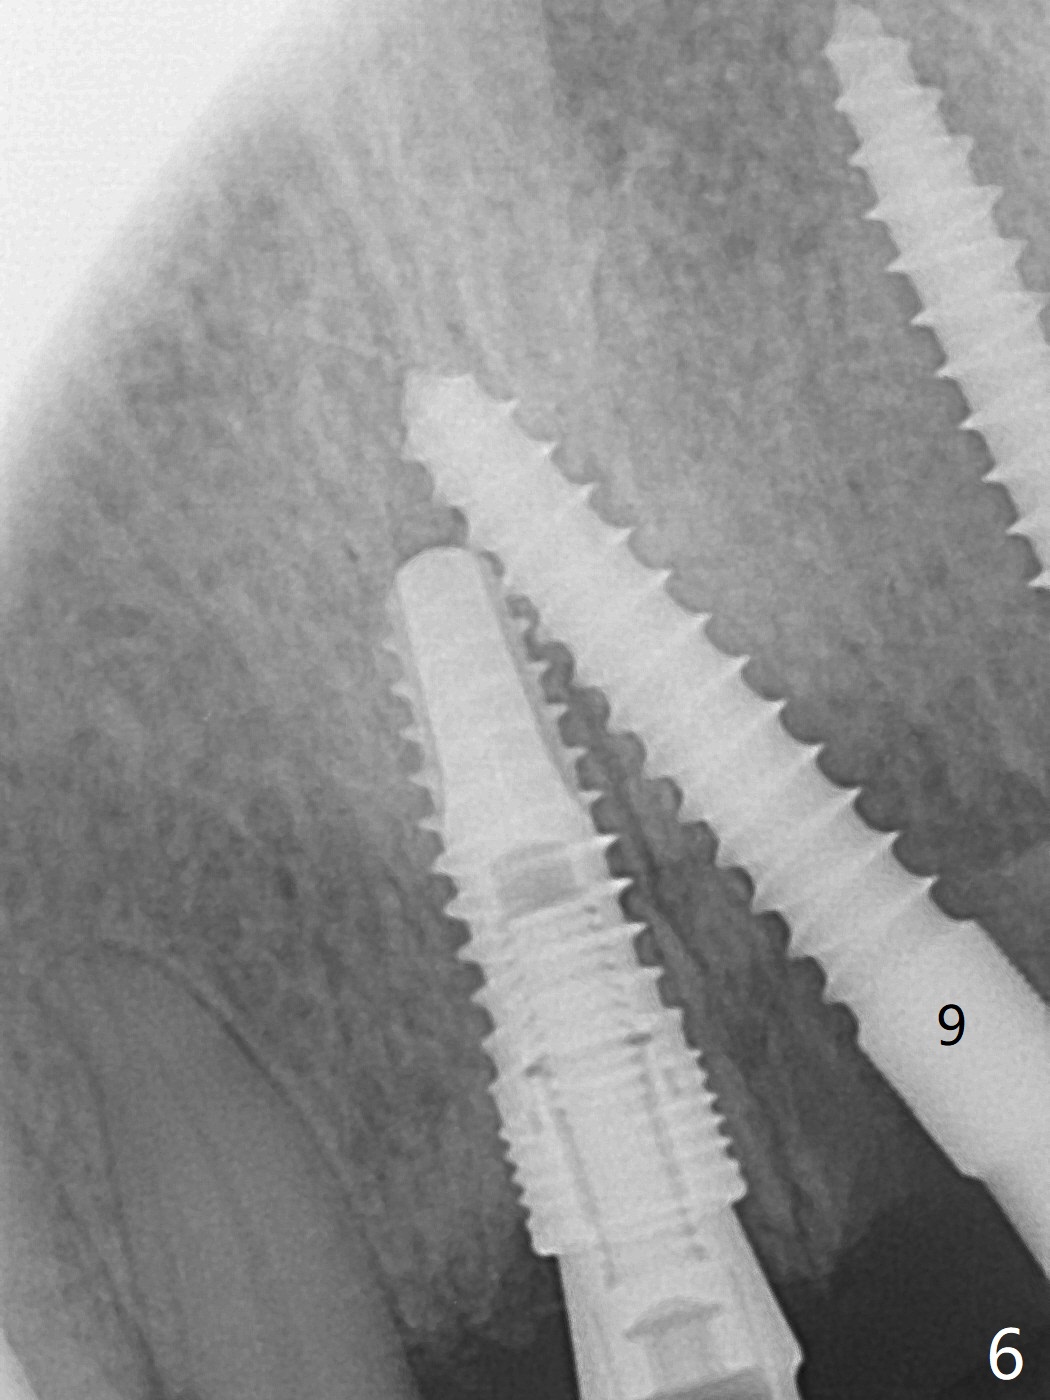

Incision shows exposure of microthreads at #9 and major threads at #10 due to buccal placement (Fig.1). There is bone palatal to the implant at #10 (Fig.2 P), to which a new implant will move. After implant removal, a narrower 1-piece implant (2.5x14(4) mm) is placed palatally at #10 (Fig.3,4) in combination of guide and free hand. At the site of #9 after implant removal, the guide is not used; a 3x17 mm angled 1-piece implant is placed with bad trajectory (Fig.5,6). After re-adjustment (Fig.7), the implant is placed at the right orientation (Fig.8). It appears that the guide is helpful. Allograft is placed mainly buccally (Fig.9,10 *), followed by a piece of collagen membrane (Fig.11). After tension release, flaps are approximated (Fig.12). The buccal gingiva at #9 and 10 recede nearly 2 months postop (Fig.13). Less recession at #9 is associated with more inflammation (Fig.14). The margin of the provisional is adjusted for gingival margin down growth and easy self cleaning with Water Pik (Fig.15). One month later, the gingival inflammation reduces, while there is no obvious buccal collapse (Fig.16,17). Impression is taken after laser gingivectomy nearly 4 months postop (Fig.18). While the gingiva around the implant at #9 is inflamed (periimplantitis?), the gingival cuff at #10 is well formed 5.5 months postop immediately before cementation (Fig.19). The buccal concavity at #10 is minimal (Fig.20). The gingival inflammation at #9 will be hopefully resolved after cementation of the final restorations (Fig.21). There appears to be new bone formation around the coronal implant threads 5.5 months postop (immediately post cementation, Fig.22). The microthreads at #9 may be not covered by the bone, the reason for the gingival erythema. The redness at #10 is asymptomatic 5.5 months post cementation (Fig.23). 粘固后两年牙槽嵴骨质并没有再生(图二十四),说明第一术中植体必须植入骨下(基台部分要长,否则难于修复),第二牙槽嵴处不应该有压力,植入2.5毫米植体,最后钻头应该是2.5毫米,骨下1-3毫米(尝试项目)。